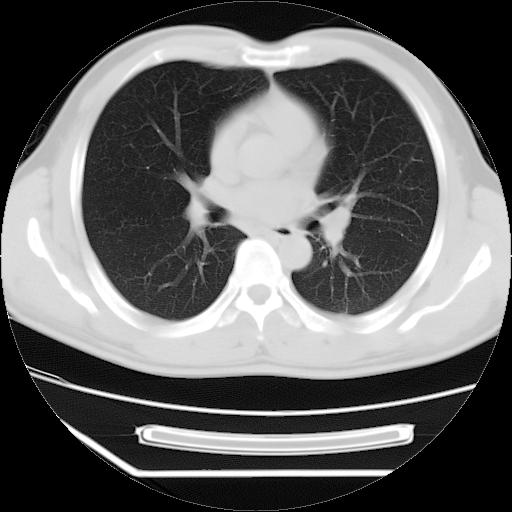

男,38岁,于2009年8月9日晚突发左侧胸痛,今x线提示左下肺阴影,为了明显确诊断,行ct检查,

血常规:嗜酸性细胞增高,单核细胞增高。

病灶发生在下叶,密度均匀,边缘模糊、毛糙,周围血管纹理增强扭曲改变,靠近胸膜处病灶胸膜反应明显。

支持考虑---球形肺炎。

左肺舌叶病变。主体病灶呈类圆形中心密度低,成液化趋势周边班片影分布

考虑肺脓肿